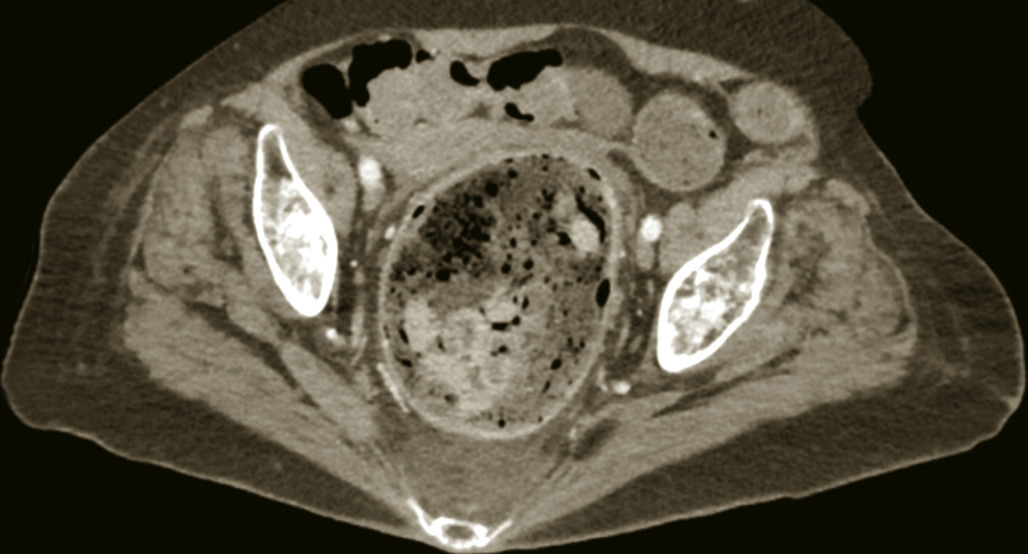

L’alitement entraîne une diminution du péristaltisme intestinal par une disparition du tonus des muscles abdominaux. La constipation est aussi favorisée par la déshydratation et par certains médicaments (anticholinergiques, opiacés). Elle peut être source de météorisme, de douleurs abdominales, d’épisodes subocclusifs, et de fécalome (fig. 1). Le fécalome peut entraîner des douleurs, une fausse diarrhée, une incontinence ou rétention urinaire, et souvent une confusion chez le sujet âgé. Le fécalome peut parfois se compliquer d’un état occlusif et d’une perforation.

La constipation doit être recherchée par une surveillance rigoureuse des selles. Elle est prévenue par une bonne hydratation des patients, une alimentation équilibrée, et une verticalisation précoce. Le traitement comprend l’utilisation de laxatifs osmotiques ou lubrifiants, des suppositoires, des lavements. Une extraction manuelle au doigt est parfois nécessaire en cas de fécalome.